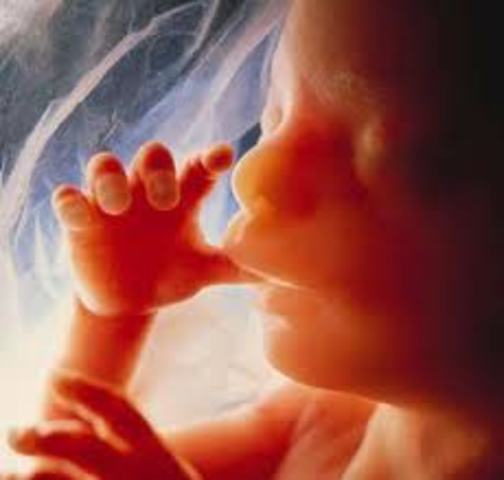

• Semana vigecima cuarta de gestación

Semana vigecima cuarta de gestación

Hola Mamá, en esta semana tu bebé es casi un humano en miniatura, sus medidas alcanzarán los 21 cm de largo y llegará a pesar unos 550 gramos, sus pulmones están en desarrollo y segregan una sustancia llamada surfactante, que le ayudarán a introducir el aire en ellos cuando nazca. Recuerda que sus diminutos órganos se han ido formando, sus sentidos también están en pleno desarrollo, por lo que ya es capaz de sentir los estímulos que va recibiendo del exterior.

Háblale para que aprenda a reconoce

• Semana vigecima quina de gestación

Semana vigecima quina de gestación

En esta semana tu bebé ya tiene muchos de los sentidos desarrollados, aunque falta la vista, comenzarán a formarse sus pestañas. Otro de los órganos que comienza a crecer más en esta semana es el oído, tu bebé comienza a percibir (oír) los primeros sonidos y a sentirse menos aislado, escuchará tu voz, ruidos ambientales y todo lo que lo rodea como los fluidos de la placenta donde se encuentra creciendo.